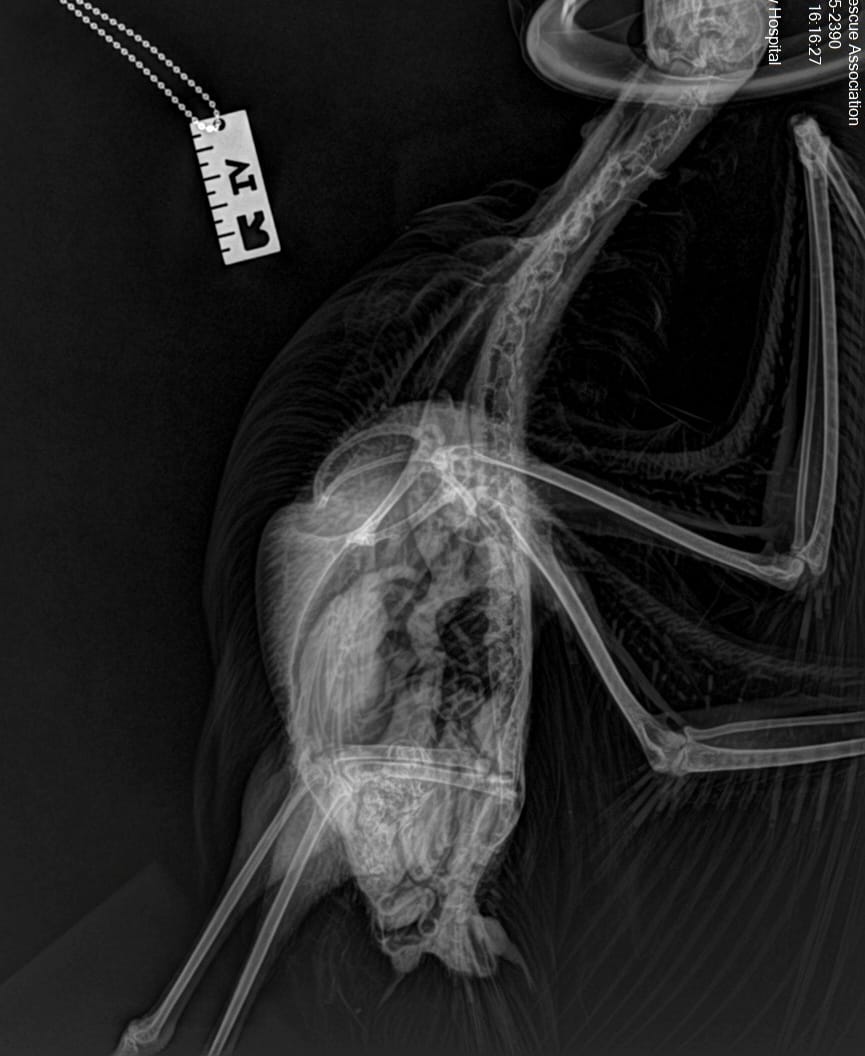

One such story was this Glaucous-winged Gull which had swallowed a skewer which presumably had chicken or some other meat on it, and in the process of trying to regurgitate it managed to drive the skewer though its throat!

The WRA team managed to successfully remove the skewer and rehab the gull. X-ray images below show the positioning of the skewer (even though the gull almost removed it on its own!). The following two images are the before and after radiographs. If you look closely enough you can see all the scar tissue it caused.